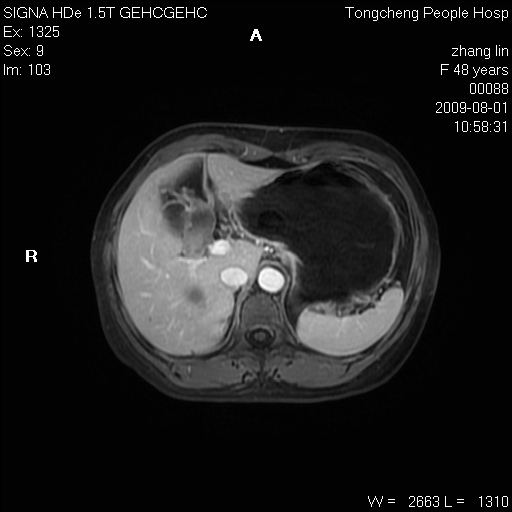

女,48岁。健康体检,彩超发现右肾占位性病变。平素健康。

临床诊断:右肾占位性病变,性质待定(囊肿?肿瘤?)。

上中腹部mr平扫+增强扫描,图像如下:

右肾上极见一类圆形病灶,t1wi呈等信号t2wi呈等高混杂信号,三期增强无强化,边界清---考虑囊肿出血。

同反相位均表现为等信号,病变无强化,考虑含蛋白的囊肿可能,弥散加权相或许有些帮助,

慢性胆囊炎